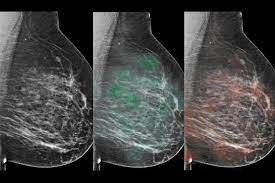

AI mammogram screening - हाल ही में एक अध्ययन से पता चला है कि मानक स्क्रीनिंग की तुलना में कृत्रिम बुद्धिमत्ता (एआई) द्वारा समर्थित मैमोग्राफी स्क्रीनिंग से स्तन कैंसर के ज्यादा मरीजों की पहचान हुई. इससे रेडियोलॉजिस्ट के स्क्रीनिंग रीडिंग का कार्यभार लगभग आधा हो गया.

AI-supported mammogram screening : चैटजीपीटी के आने के बाद हर क्षेत्र में अब आर्टफिशियल इंटेलीजेंस यानी एआई के इस्तेमाल की चर्चा शुरू हो गई है. यह नतीजे भी अच्छे दे रहा है. हाल ही में एक अध्ययन से पता चला है कि मानक स्क्रीनिंग की तुलना में कृत्रिम बुद्धिमत्ता (एआई) द्वारा समर्थित मैमोग्राफी स्क्रीनिंग से स्तन कैंसर के ज्यादा मरीजों की पहचान हुई. इससे विकिरण चिकित्सकों (रेडियोलॉजिस्ट) के स्क्रीनिंग रीडिंग का कार्यभार लगभग आधा हो गया. ‘द लांसेट ऑन्कोलॉजी’ जर्नल में प्रकाशित एक नये शोध में यह जानकारी सामने आयी है. स्वीडन के लुंड विश्वविद्यालय के नेतृत्व में किये गए अध्ययन से पता चला कि स्तन कैंसर की जांच के लिए एआई-समर्थित मैमोग्राफी, मानक डबल स्क्रीनिंग के विकल्प के रूप में ज्यादा सटीक, सुरक्षित और कुशल है.

शोध में अध्ययन के लिए लगभग 80,000 महिलाओं को शामिल किया गया तथा उन्हें दो अलग-अलग समूहों में बांट दिया गया. 40,003 महिलाओं के एक समूह को एआई-समर्थित स्क्रीनिंग तथा 40,030 महिलाओं के दूसरे समूह को मानक स्क्रीनिंग प्रक्रिया से गुजारा गया. शोध में एआई-समर्थित स्क्रीनिंग से 244 महिलाओं (28 फीसदी) में कैंसर पाया गया, जबकि मानक स्क्रीनिंग से 203 महिलाओं (25 फीसदी) में कैंसर का पता चला. शोध के परिणामस्वरूप एआई समर्थित स्क्रीनिंग से कैंसर के 41 अधिक मरीजों का पता चला.

विश्वविद्यालय में डायग्नोस्टिक रेडियोलॉजी में प्रमुख शोधकर्ता और सहायक प्रोफेसर क्रिस्टीना लैंग ने कहा, हमने पाया कि एआई का उपयोग करने से मानक स्क्रीनिंग की तुलना में फाॅल्स पॉजिटिव को प्रभावित किये बिना 20 फीसदी (41) अधिक कैंसर मरीजों का पता चला. स्क्रीनिंग में फाॅल्स पॉजिटिव तब होता है जब एक महिला को फिर से बुलाया जाता है लेकिन स्क्रीनिंग के बाद उसे कैंसर के संदेह से मुक्त कर दिया जाता है.

शोधकर्ताओं ने कहा कि दोनों अध्ययन में फाॅल्स पॉजिटिव दर डेढ़ फीसदी थी. इसके अलावा, रेडियोलॉजिस्ट के लिए स्क्रीन-रीडिंग कार्यभार में 44 फीसदी की कमी पायी गई. अध्ययन में एआई-समर्थित स्क्रीनिंग, मानक स्क्रीनिंग 83,231 की तुलना में 46,345 थी.